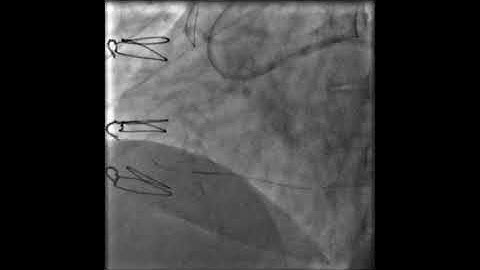

Case 119: PCI Manual - Retrograde for non-CTO PCI